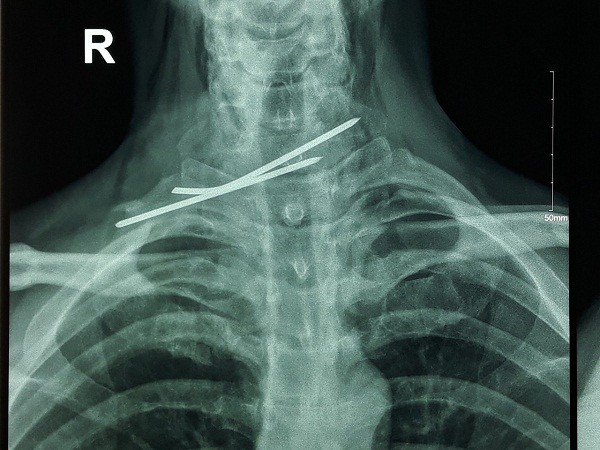

Hình ảnh X-quang cho thấy cây kim đâm xuyên thực quản và khí quản bệnh nhân - Ảnh: Sức khỏe Đời sống

Qua thăm khám và làm các cận lâm sàng, bác sĩ chẩn đoán bệnh nhân có dị vật vùng cổ do đinh Kirschner kết hợp xương đòn đâm xuyên thực quản và khí quản.

Các bác sĩ đã phẫu thuật lấy đinh và khâu lại thực quản, khí quản. Sau phẫu thuật, sức khỏe bệnh nhân ổn định, ăn uống được, theo Trí thức trẻ đưa tin.

Trao đổi với báo Sức khỏe Đời sống, bác sĩ cho hay, bệnh nhân đã được phẫu thuật kết hợp xương bằng các dụng cụ (đinh, vít...) nên đi tái khám đúng theo sự hướng dẫn của thầy thuốc. Tránh trường hợp không tái khám hoặc tái khám quá muộn (như trường hợp này). Các dụng cụ như đinh, vít nhỏ sẽ di chuyển nhiều nơi đâm xuyên các cơ quan gây nguy hiểm, nếu đâm xuyên các mạch máu lớn còn nguy hiểm tính mạng...